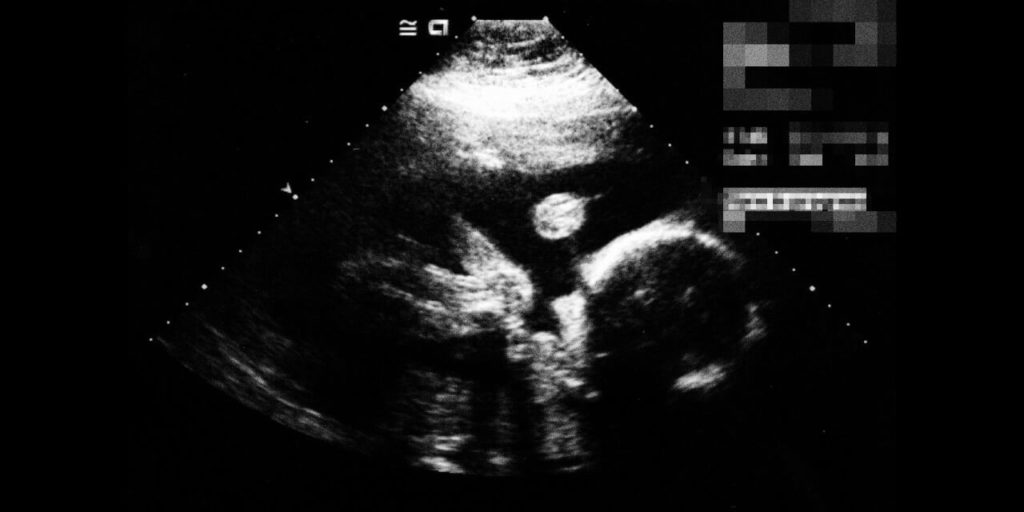

Забеременела снова я через три года после перевязки. В мае 2015 года на меня стала накатывать усталость, иногда мучила тошнота по утрам, но месячные шли как по расписанию, поэтому я и не думала о беременности. В июне стало сильно тошнить от запаха еды — тогда-то я и запаниковала. Сделала три простых теста на беременность: первые два — отрицательные, последний — положительный. Потом купила электронный — тоже положительный. После этого я обратилась в женскую консультацию. Мне сделали УЗИ, но ничего не увидели. На втором УЗИ, уже в перинатальном центре, беременность подтвердили. Мы были в шоке, но ребенка решили оставить.

Всю беременность я дико боялась за ребенка: такой путь пройден — даже дышать страшно. На восьмой неделе открылось сильное кровотечение. Оказалось, что с ЭКО так бывает. Также был риск рубцовой беременности. Но, к счастью, все обошлось. На первом УЗИ мне дали послушать сердцебиение малыша. Знаете, я помню стук сердца каждого своего ребенка, но таких эмоций, как в тот раз, у меня еще не было. Я расплакалась, хотя человек не особо эмоциональный. Муж подкалывал меня, что эта беременность сделала меня такой слабохарактерной.